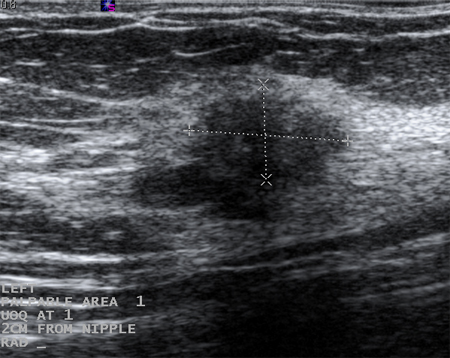

Ultrasonographic image of a complex cyst

Courtesy of Dr Lane Roland, University of Louisville; used with permission